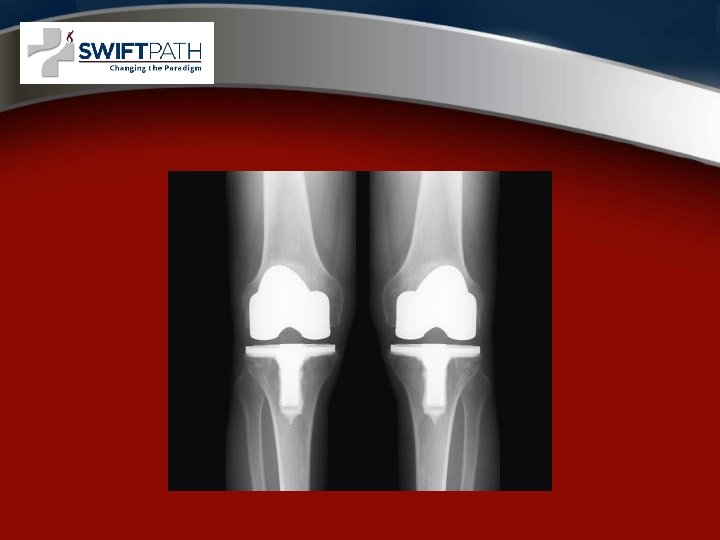

Surgical options • Arthroscopy • Partial Knee Replacement • Total Knee Replacement

COMPUTER NAVIGATION AND ROBOTIC NAVIGATION IN JOINT REPLACEMENT

Surgical Technique • General principles • Minimally Invasive Surgery “MIS”, “Miniincision” • Computer Assisted Surgery or “Navigation” • Robotic - MAKOPLASTY

MIS Knee Replacement • • Faster Recovery Improved Quads Function Less Pain Smaller Incisions Better ROM More Radiographic Outliers Computer Navigation Recommended